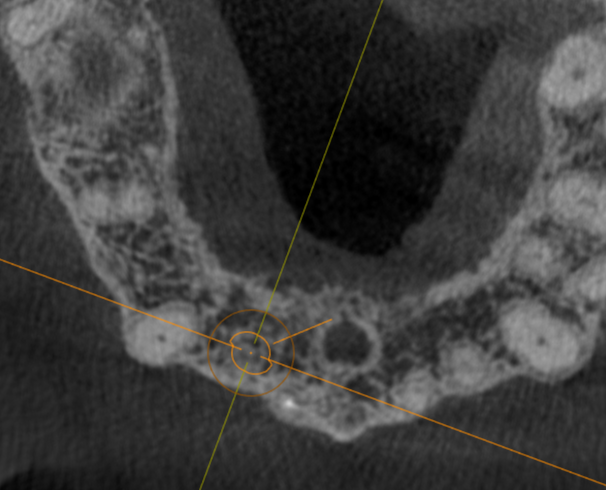

Immediate #7

Thoughts on angulation, depth, F/L position? I feel like its too deep, but wanted to at least be bone level on the lingual. Use his old crown as a temp if I achieve enough torque?

In planned position, the apical third awfully close to the cortical plate.

This is a 3.75 x 13. Will be placing a 3.5 x 13